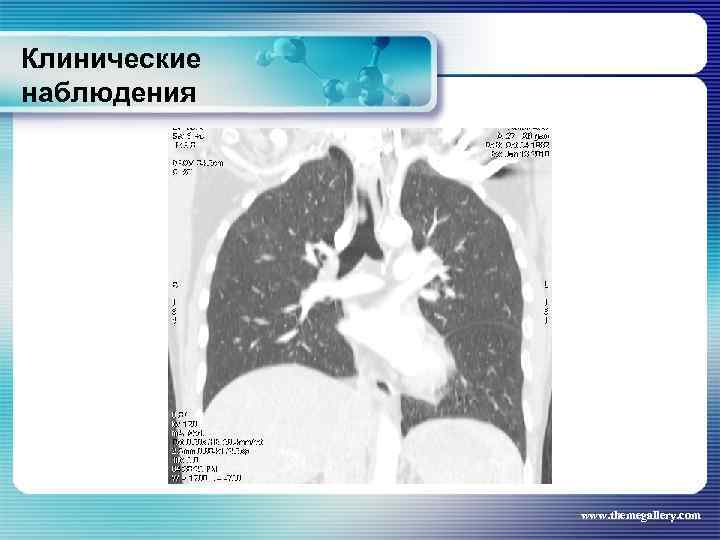

Клинические наблюдения Тот же пациент Выполнена эндоскопическая торакоскопия с открытой биопсией образования переднего средостения. Гистологическое заключение: лимфома Ходжкина, нодулярный склероз. При СКТ ниже диафрагмы патологических процессов не выявлено. Сформулирован клинический диагноз: лимфома Ходжкина, нодулярный склероз, стадия IIБ, с поражением средостения, парастернальных и надключичных лимфатических узлов слева. Была начата ПХТ при программе ВЕАСОРР, но после II цикла появилась одышка и лихорадка. При СКТ – блеомицетиновый пульмонит www. themegallery. com

Клинические наблюдения Тот же пациент Выполнена эндоскопическая торакоскопия с открытой биопсией образования переднего средостения. Гистологическое заключение: лимфома Ходжкина, нодулярный склероз. При СКТ ниже диафрагмы патологических процессов не выявлено. Сформулирован клинический диагноз: лимфома Ходжкина, нодулярный склероз, стадия IIБ, с поражением средостения, парастернальных и надключичных лимфатических узлов слева. Была начата ПХТ при программе ВЕАСОРР, но после II цикла появилась одышка и лихорадка. При СКТ – блеомицетиновый пульмонит www. themegallery. com